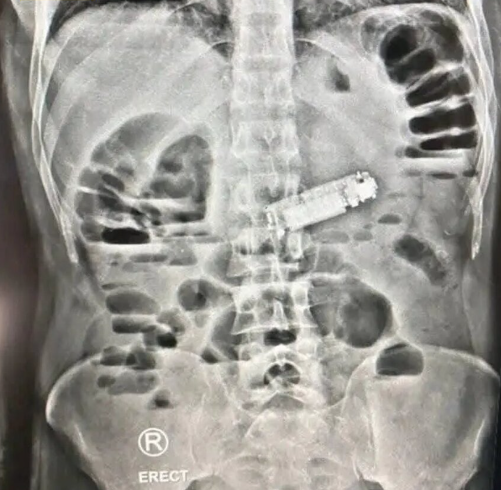

وصل المريض إلى المستشفى في حالة حرجة، يعاني من إعياء شديد، وقيء مستمر، وآلام حادة في البطن. وعلى الفور، أجريت له الفحوصات الطبية اللازمة بما في ذلك الأشعة، التي كشفت عن وجود جسم غريب يسد فتحة البواب في المعدة. المفاجأة كانت أن هذا الجسم الغريب هو هاتف محمول صغير ابتلعه المريض.

أجرى الفريق الطبي عملية جراحية عاجلة لاستخراج الهاتف، وتمت العملية بنجاح كامل ودون حدوث أي مضاعفات. المريض استعاد وعيه بعد الجراحة في قسم الإفاقة، وحالته الصحية الآن مستقرة، مع بقائه تحت الملاحظة الطبية للتأكد من تعافيه التام.